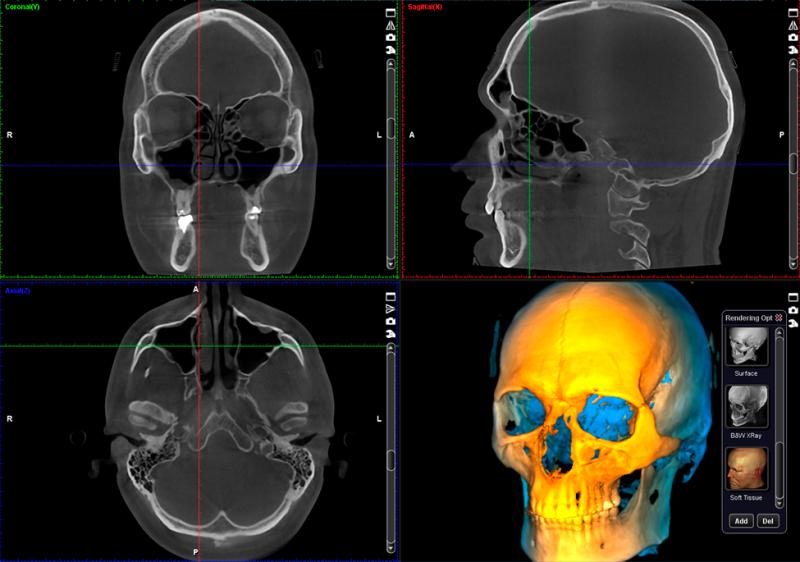

In today’s fast-paced healthcare world, speed, accuracy, and security in medical imaging are more important than ever. Hospitals, clinics, and diagnostic centers depend on reliable imaging tools to make confident decisions and deliver the best possible care to patients. This is where ALM Viewer stands out as a complete, modern solution. Designed with healthcare professionals in mind, ALM Viewer combines cutting-edge technology with user-centered design to simplify imaging workflows, protect sensitive data, and improve diagnostic accuracy.

ALM Viewer is a DICOM (Digital Imaging and Communications in Medicine) viewer that makes it easy for healthcare providers to access, manage, and share medical images securely. It supports high-resolution images, advanced visualization, and smooth performance across devices such as desktops, tablets, and smartphones. Whether you are a radiologist analyzing complex scans or a clinician reviewing images for diagnosis, ALM Viewer ensures you have the right tools at your fingertips.

Crystal-Clear Imaging

High-resolution images are vital for accurate diagnoses. ALM Viewer provides detailed imaging with advanced visualization features, ensuring radiologists and specialists can identify even the smallest details confidently.

• 3D Segmentation – Identify anatomical structures in three dimensions for better accuracy in research and diagnostics.

• Hanging Protocols – Customize display layouts with multi-planar reformatting and multi-modal fusion for precise image interpretation.

• GPU-Accelerated Rendering – Handle complex image rendering quickly with powerful graphics processing.